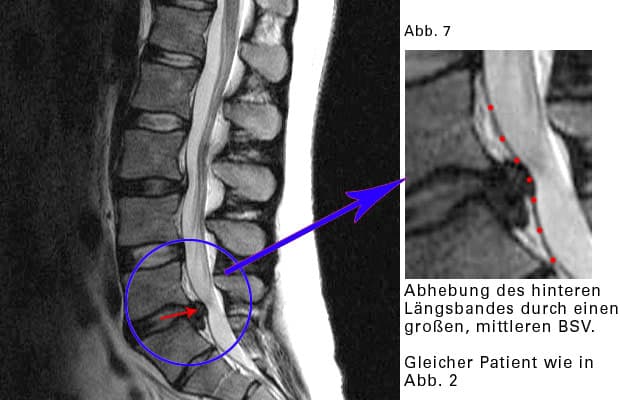

Reizung des hinteren Längsbandes

Ein kräftiges Band überzieht die hinteren Flächen der Wirbelkörper und die Bandscheiben. Es begrenzt die bauchwärts gelegene Wand des Wirbelkanales (sh Bild).

Das hintere Längsband wird durch einen BSV „ausgebeult“. In jedem Band des Körpers befinden sich Nervenrezeptoren. Sie registrieren Spannungen und Schmerzen und leiten ihre Messergebnisse weiter an das Rückenmark, an das Gehirn. Wird das hintere Längsband „ausgebeult“ und durch Bücken zunehmend gedehnt, dann „funken“ die Nervenrezeptoren: es schmerzt.